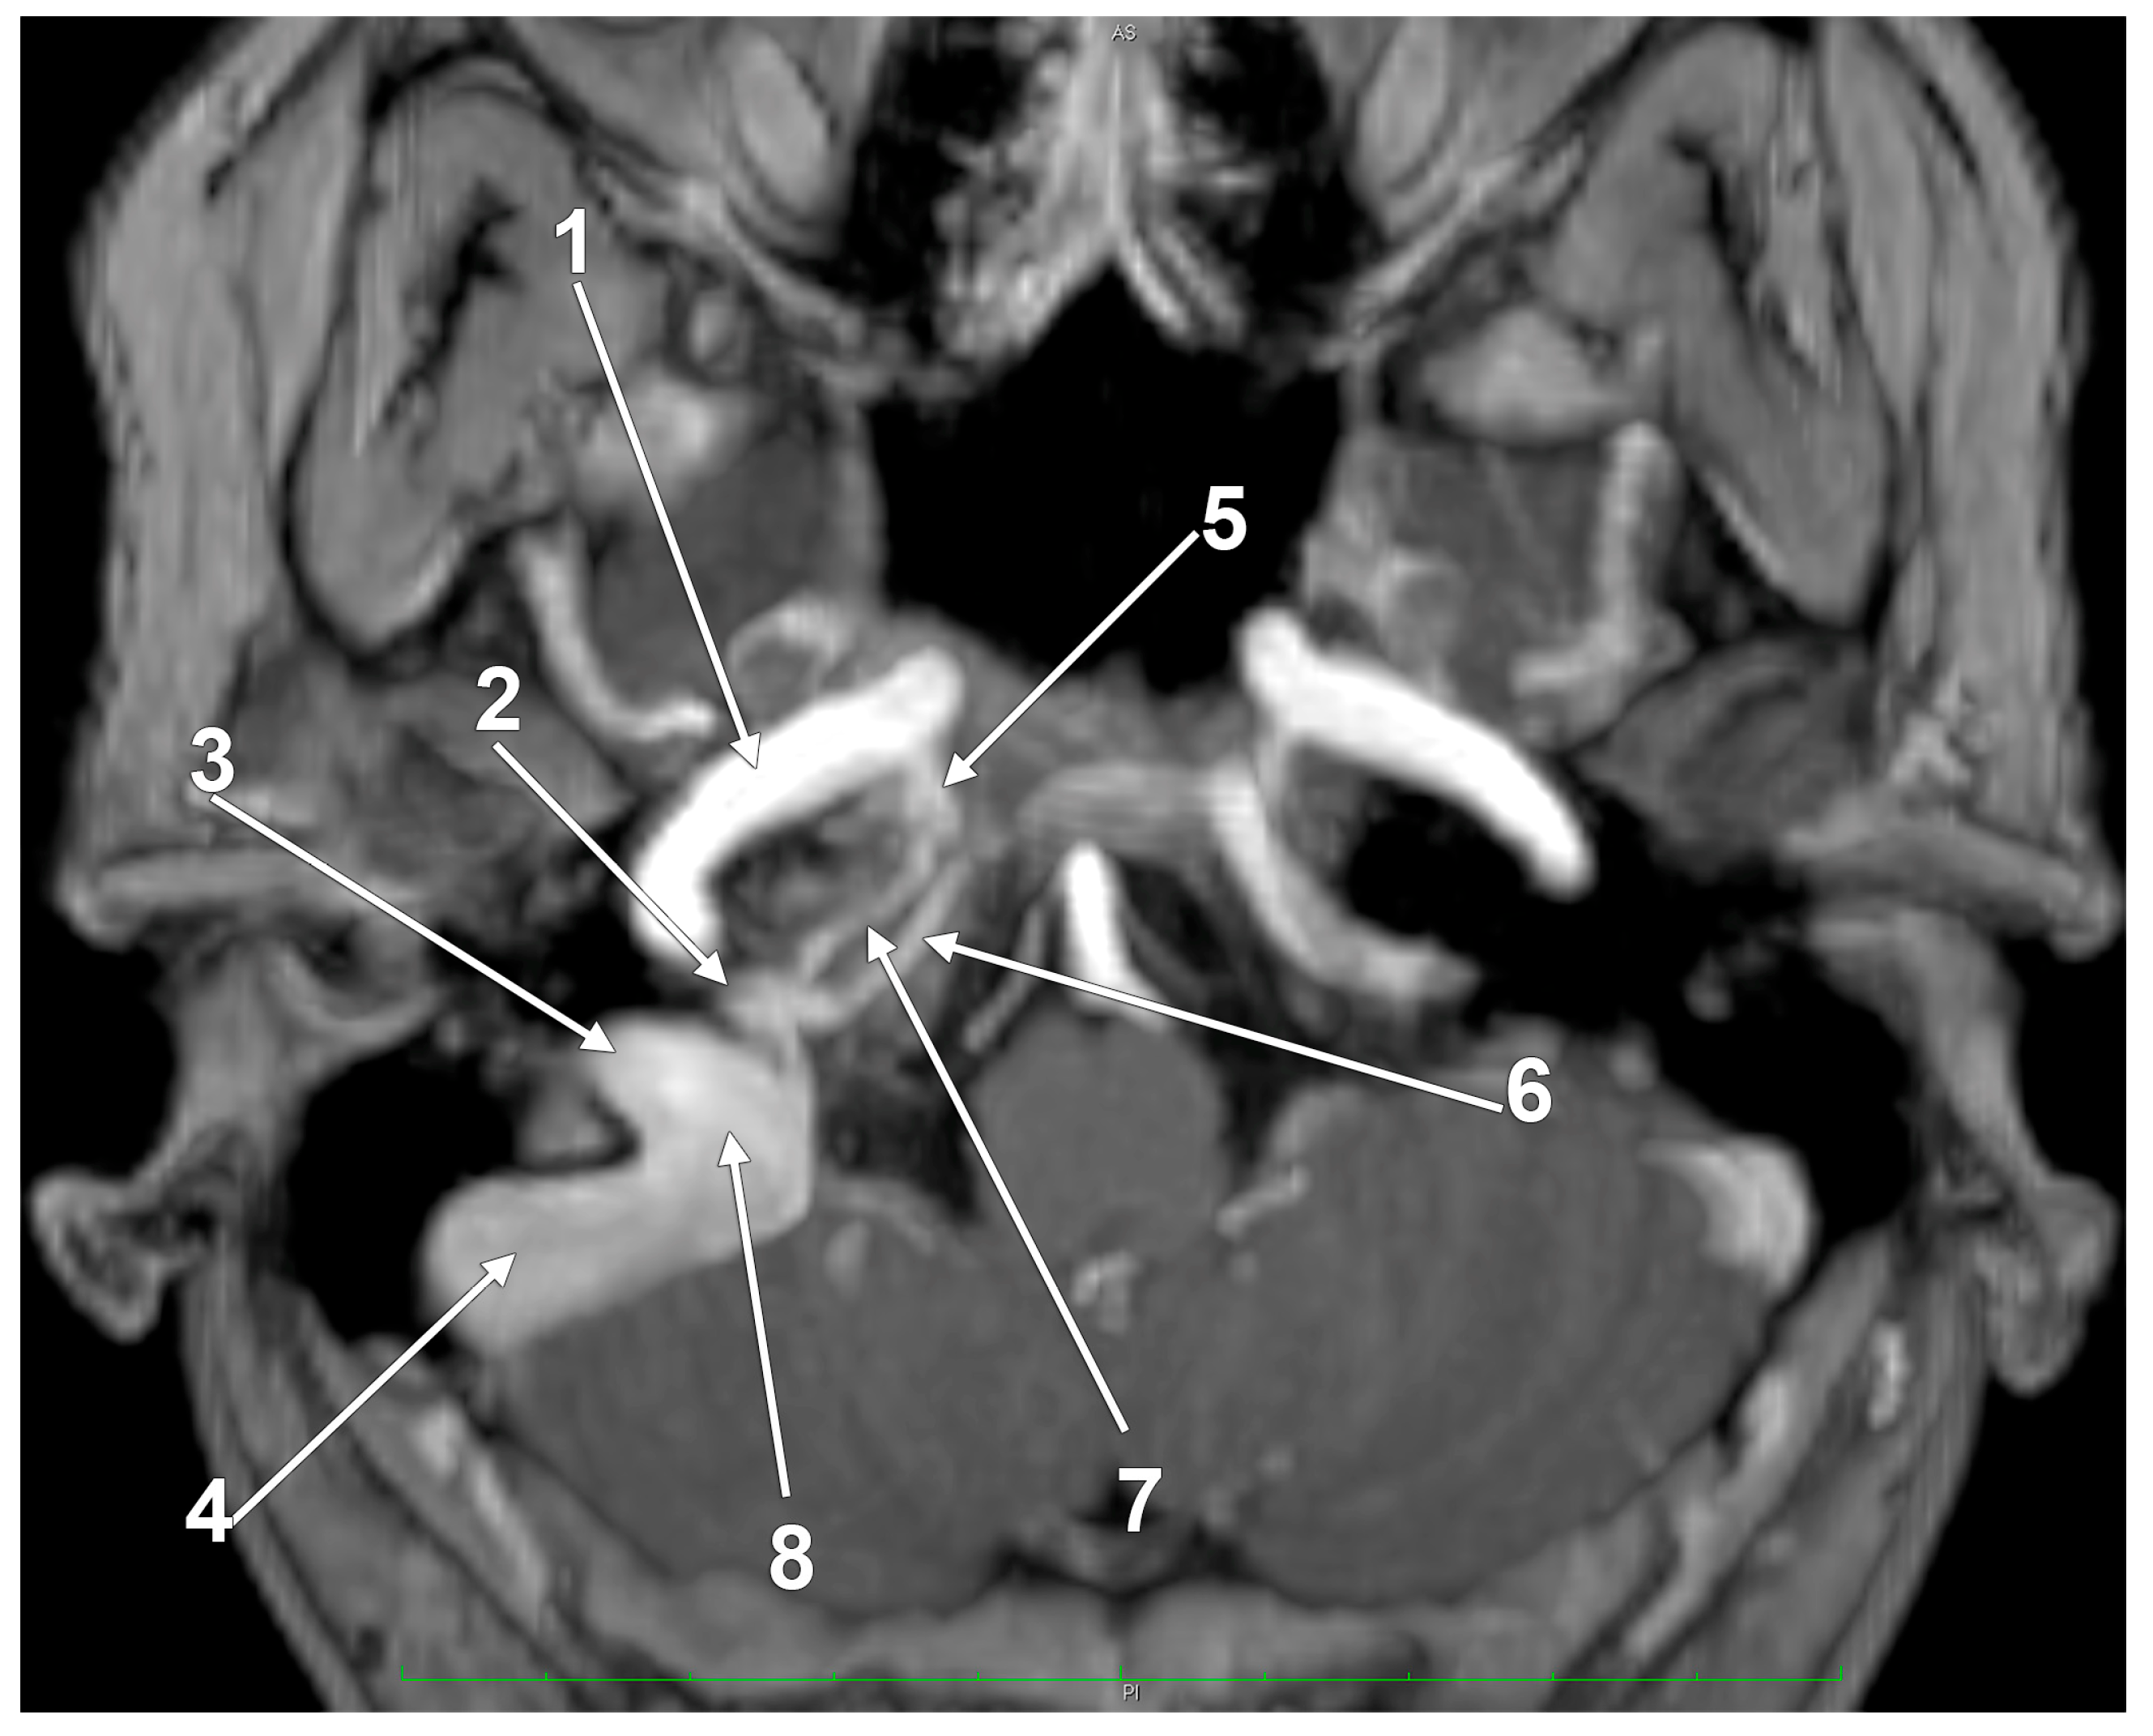

- Spittau, B.; Millan, D.S.; El-Sherifi, S.; Hader, C.; Singh, T.P.; Motschall, E.; Vach, W.; Urbach, H.; Meckel, S. Dural arteriovenous fistulas of the hypoglossal canal: Systematic review on imaging anatomy, clinical findings, and endovascular management. J. Neurosurg. 2015, 122, 883–903. [Google Scholar] [CrossRef]

- Yamada, H.; Mizutani, K.; Akiyama, T.; Toda, M. Extracranial prevertebral venous network of the craniocervical junction: CT-digital subtraction venography analysis. Neuroradiology 2022, 64, 2227–2233. [Google Scholar] [CrossRef]

- Takemoto, K.; Tateshima, S.; Rastogi, S.; Gonzalez, N.; Jahan, R.; Duckwiler, G.; Vinuela, F. Onyx embolization of anterior condylar confluence dural arteriovenous fistula. BMJ Case Rep. 2013, 2013. [Google Scholar] [CrossRef]

- Mortazavi, M.M.; Tubbs, R.S.; Riech, S.; Verma, K.; Shoja, M.M.; Zurada, A.; Benninger, B.; Loukas, M.; Cohen Gadol, A.A. Anatomy and pathology of the cranial emissary veins: A review with surgical implications. Neurosurgery 2012, 70, 1312–1318, discussion 1318–1319. [Google Scholar] [CrossRef]